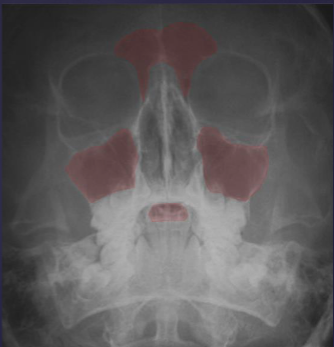

water projection is used for what

evaluating maxillary sinuses